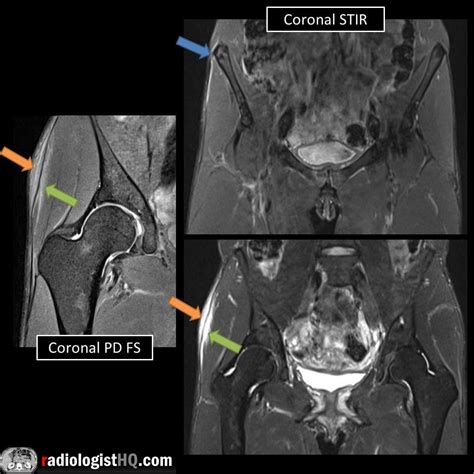

Diagnosing an IT Band Tear

Diagnosing an IT band tear typically involves a combination of physical examination and imaging tests. A healthcare provider will:

• Assess the affected area for pain, swelling, and tenderness.

• Evaluate the range of motion and strength of the knee and hip.

• Perform specific tests, such as the Noble compression test, to confirm the diagnosis.

• Order imaging tests, such as X-rays, MRI, or ultrasound, to visualize the extent of the injury.